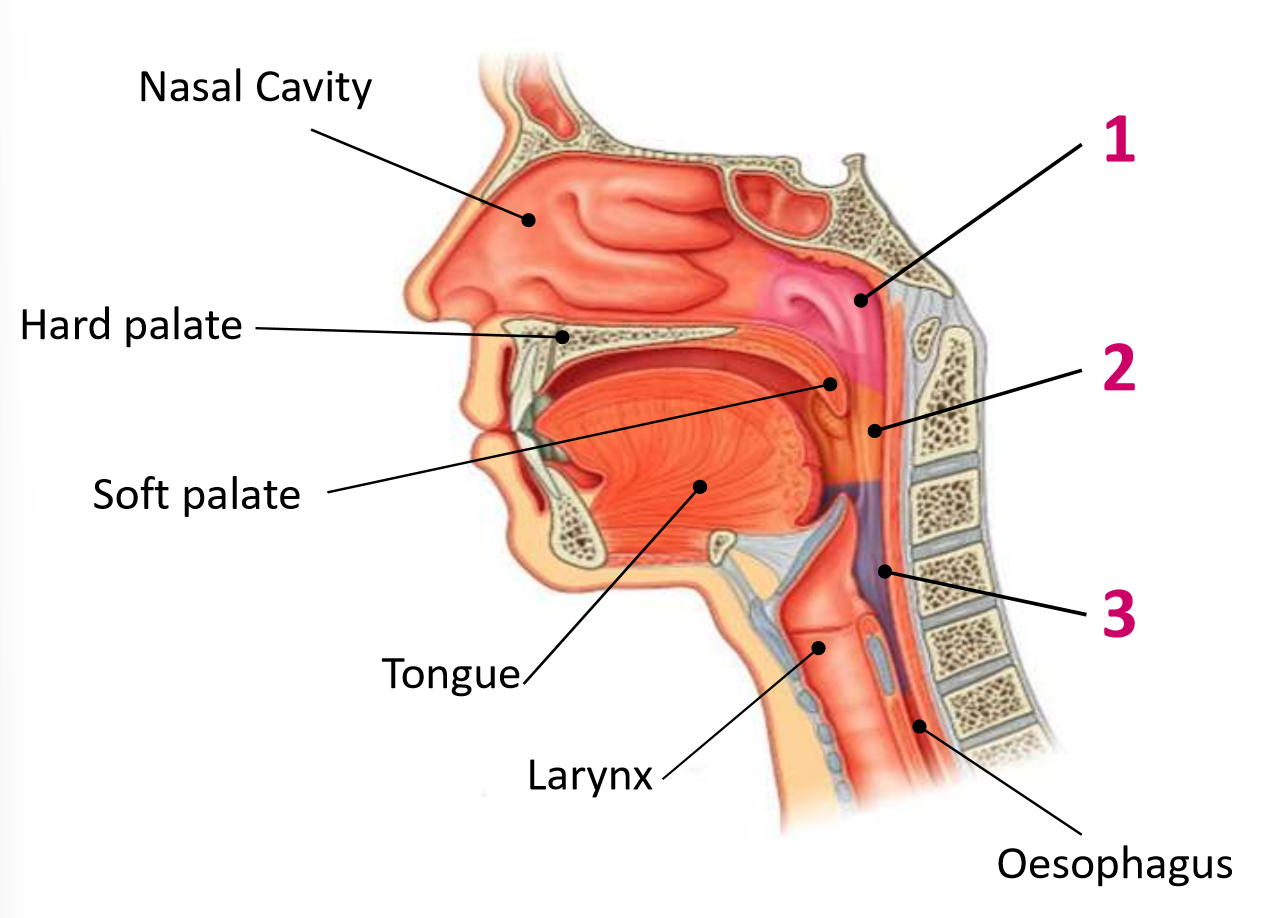

Which area of the head and neck do 1, 2, and 3 make?

pharynx

What region is 1?

nasopharynx

What region is 2?

oropharynx

What region is 3?

laryngopharynx